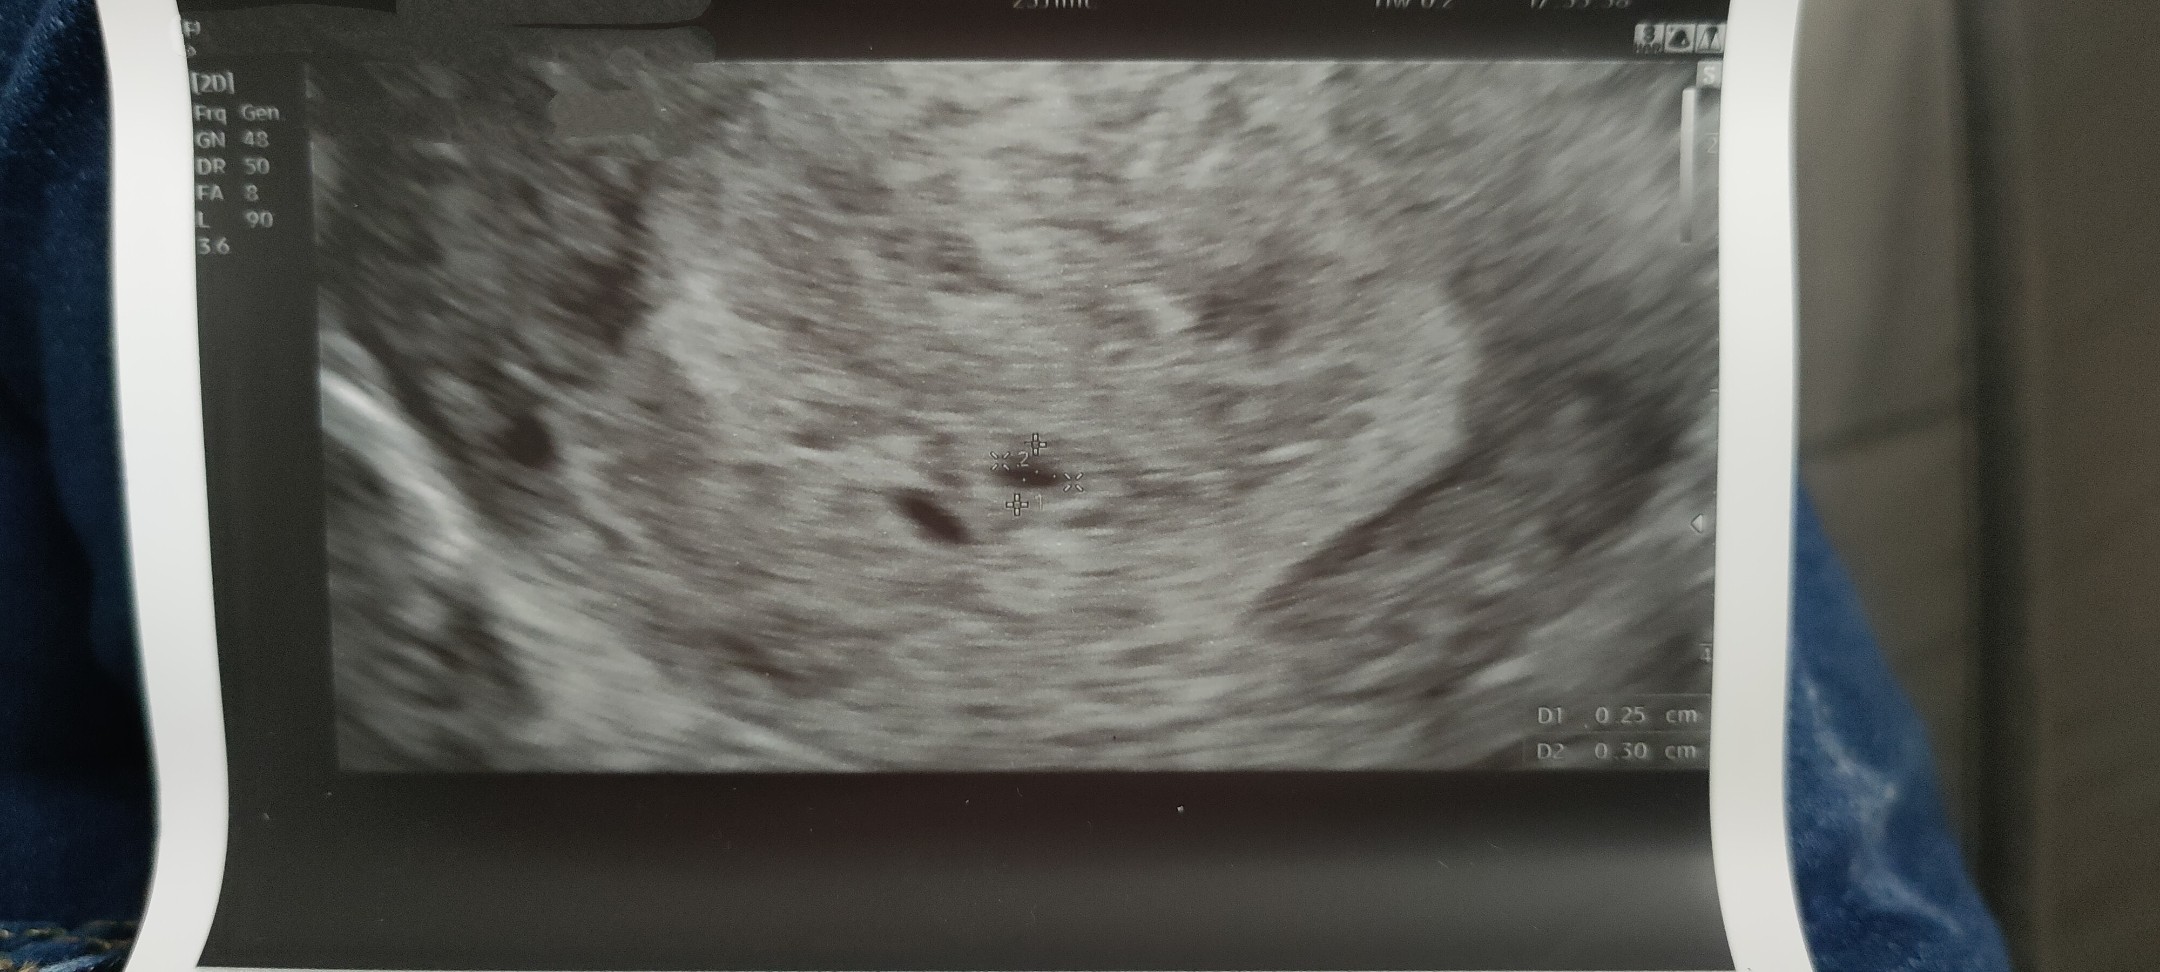

Dziewczyny wczoraj byłam na USG, wiem że to dopiero 4 tydzień ale potrzebowałam L4. Lekarz stwierdził że to na górze to pęcherzyk ciążowy a to poniżej to co to? Z rozpędu zapomniałam zapytać. Dziękuję za pomoc

• IMG_20211222_103616.jpg

IMG_20211222_103616.jpg

388,7 KB · Wyświetleń: 160